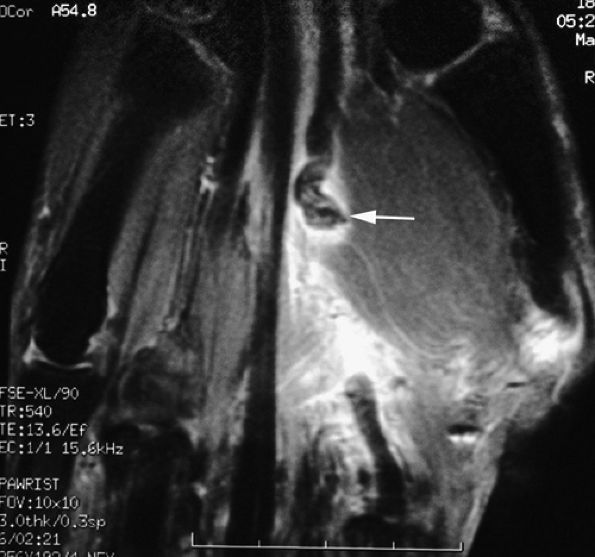

FIGURE 11.52 ● Elongation of a tendon callus of the flexor pollicis longus. Sagittal (A) and axial (B) post-contrast T1-weighted images show a thickened callus 1 cm in length with predominant scar tissue (arrows). Eight months later, sagittal (C) and axial (D) post-contrast T1-weighted images demonstrate the maturation process with thinning of the callus and predominant low-signal-intensity mature tissue (arrows).